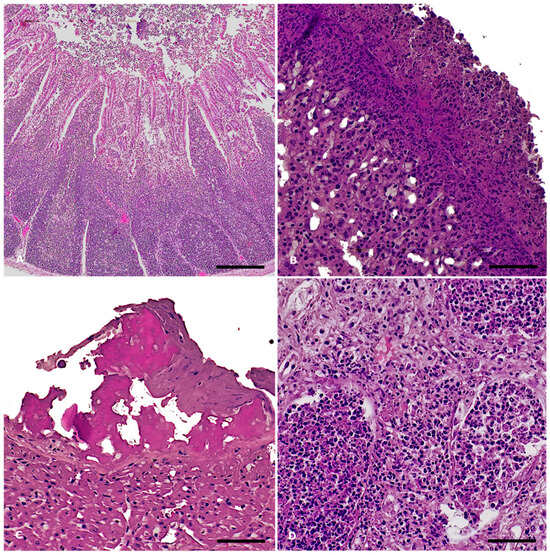

3.2.2. Histopathology